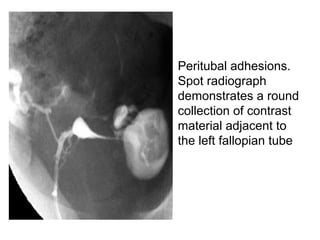

• Peritubal adhesions.

Spot radiograph

demonstrates a round

collection of contrast

material adjacent to

the left fallopian tube

• Peritubal adhesions. Spotradiograph demonstrates a round collection of contrast material adjacent to the left fallopian tube